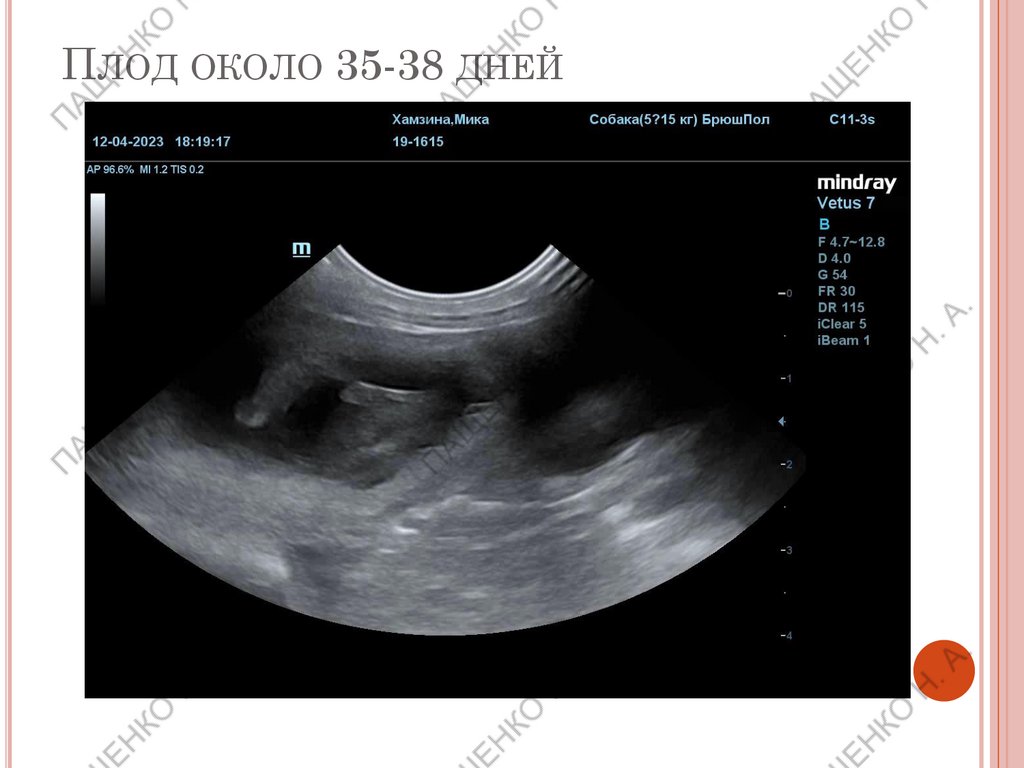

ПЛОД ОКОЛО 35-38 ДНЕЙ

Наличие плодов определяется с 21 по 35 день. Тогда же

считается и приблизительное количество. Абсолютно точное

количество плодов по УЗИ не всегда возможно (особенно на

поздних сроках). Важно информировать владельцев!

При определении описывается приблизительное кол-во

плодов, ЧСС плодов (если возможно), считается срок

беременности по формулам.

Диаметр плодного

пузыря необходимо

замерять без

толщины стенок.

Бипариетальный

размер черепа

снимать строго в

ровном положении.